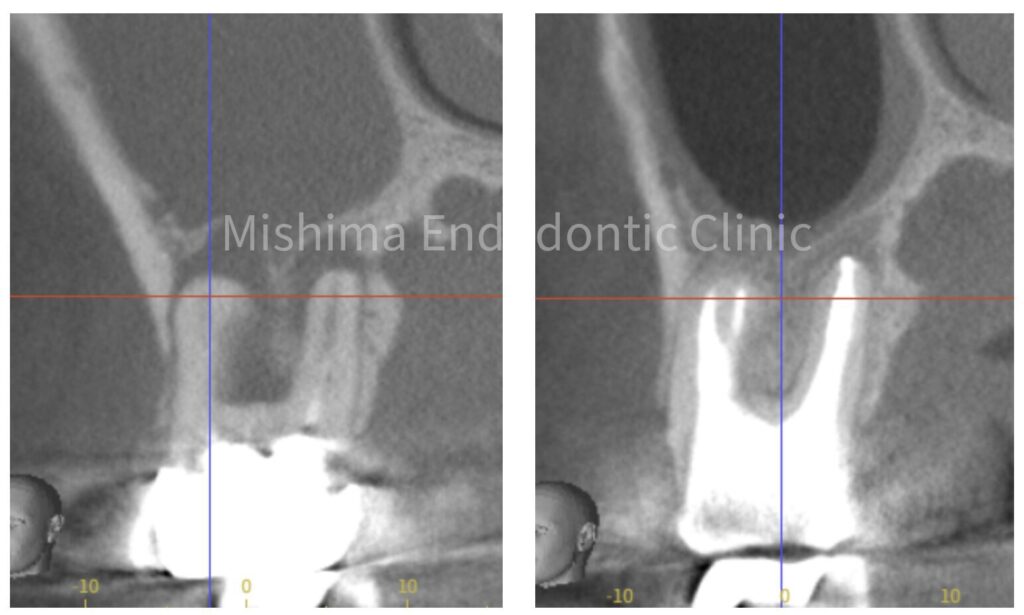

CBCT 術前術後

上顎洞粘膜は改善